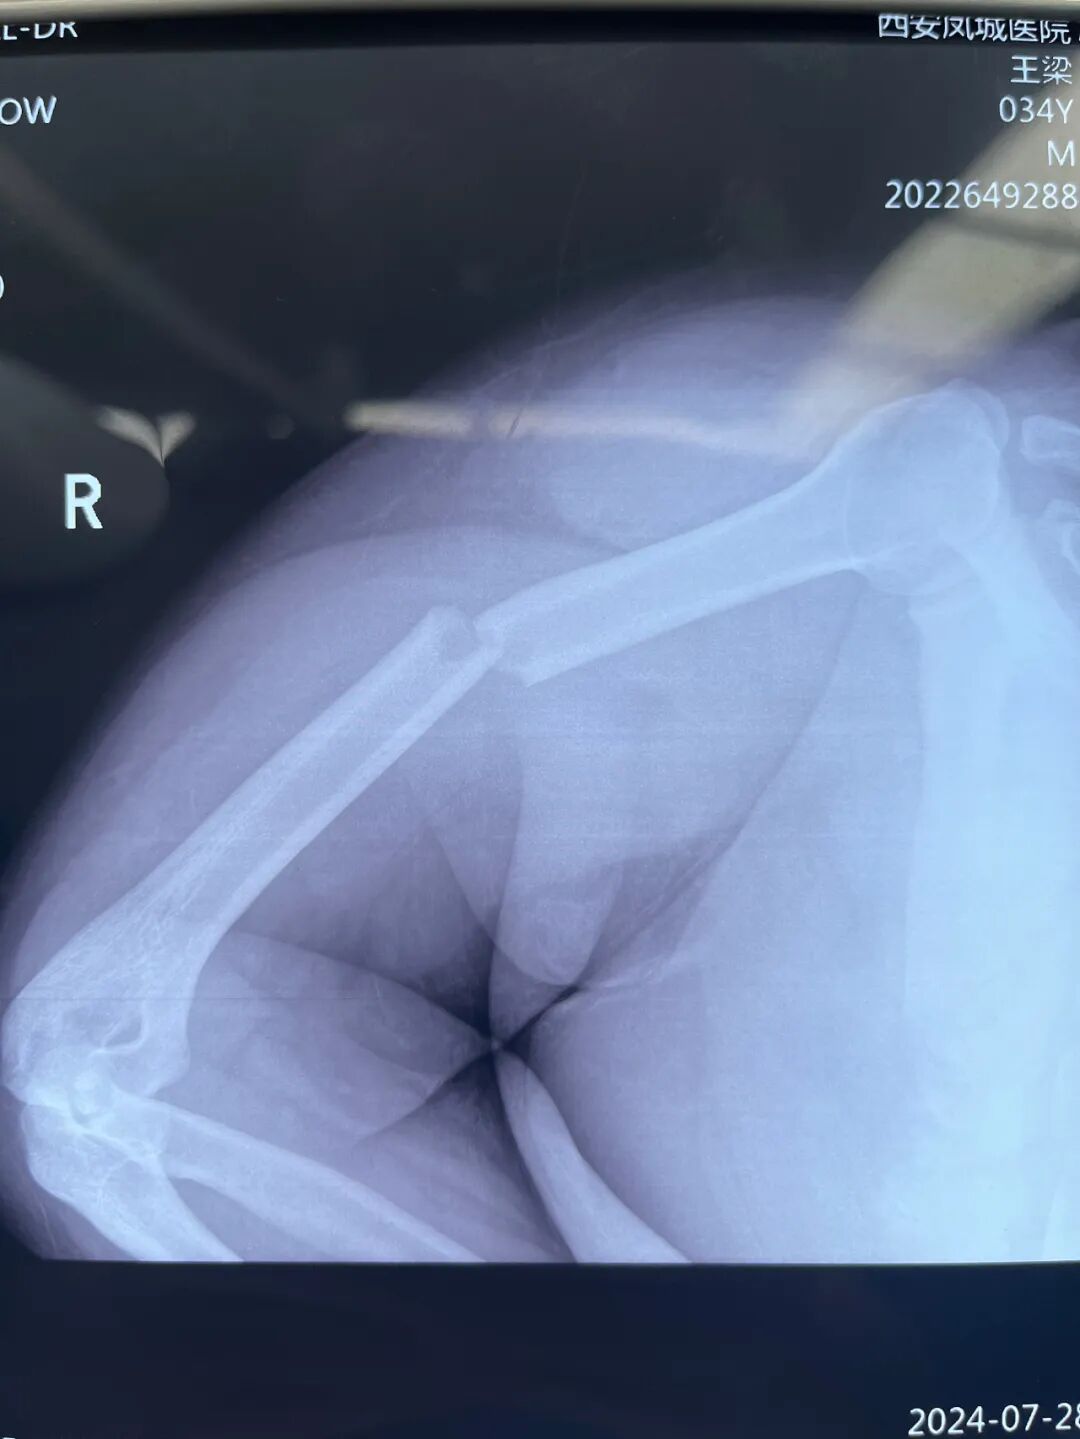

患者王先生(化名),患有呼吸暂停综合症,体重达260余斤。长期以来,每至夜间睡眠,他都需借助呼吸机辅助呼吸。一次意外摔伤,致使其右肱骨骨折。王先生曾辗转多家三甲医院寻求治疗,却皆因体重过重以及呼吸暂停综合症而被拒予手术。多方探寻后,他最终来到陕西冶金医院骨科就诊,并带着呼吸机入院。

经过深入研讨和严谨分析,最终确定了完善的手术和麻醉方案。随后,在全麻状态下,成功为王先生实施了右侧肱骨干骨折髓内钉固定术。手术与麻醉过程进展十分顺利。术后,王先生安全度过了呼吸暂停危险期。

△ 右侧肱骨干骨折髓内钉固定术术后